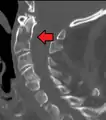

A fracture of the base of the dens as seen on CT

Type 2 dens fracture